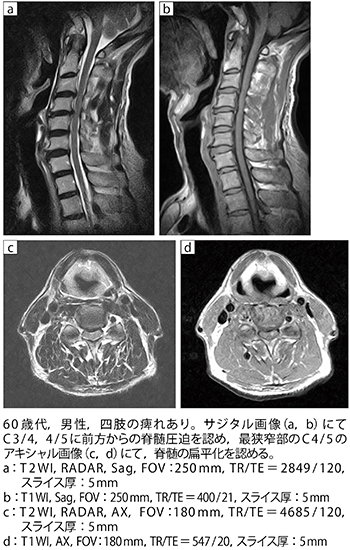

■症例1:頸椎症性脊髄症